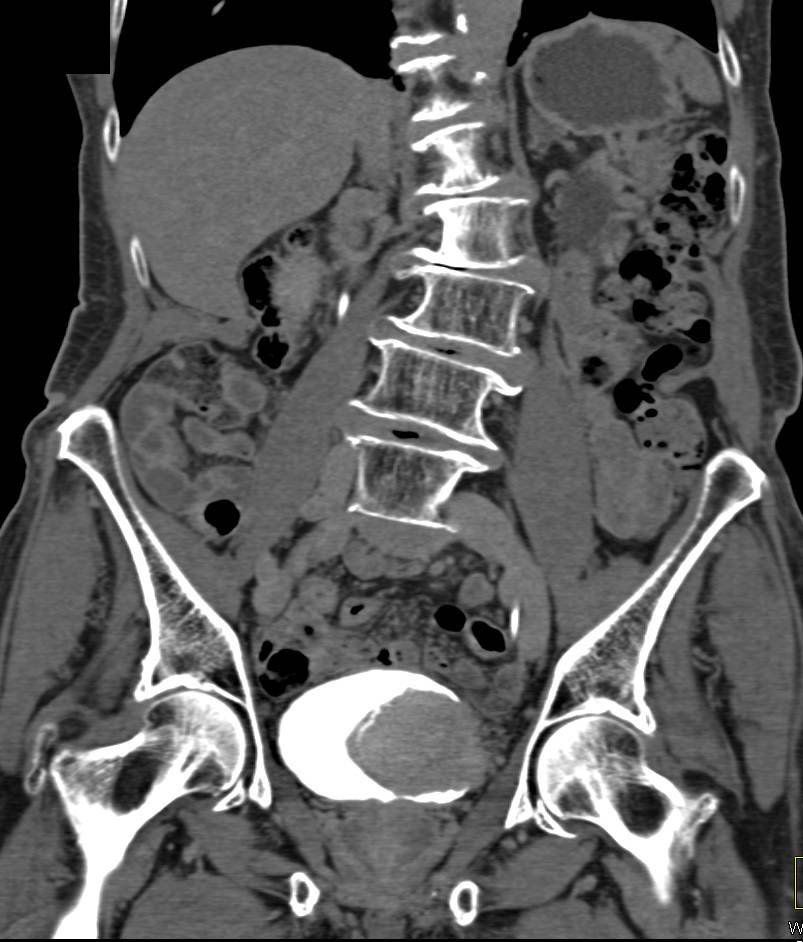

Primjer ispitivanja hematurije CT urografijom kroz slučajeve!

Slučaj 1. Karcinom urotelnih ćelija.

Slučaj 2. Karcinom mokraćne bešike.

Slučaj 3. Kamenci u bubrezima